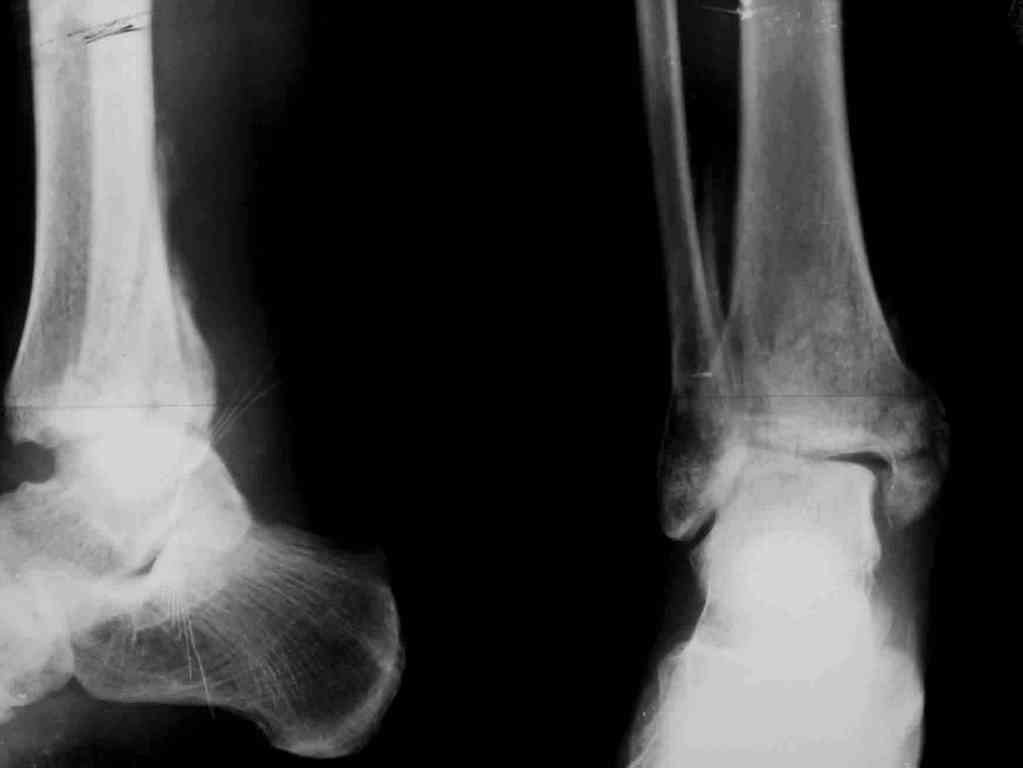

Вторая пациентка 34 лет, перелом получала в Испании, где от операции отказалась, дома по приезду сняла скотчкаст и лечилась у костоправов, нагрузка с 3 недели. Операция через 3 мес после травмы. Остеотомия м-б кости, фиксация пластиной, восстановление МБС. Так как медиальная лодыжка подтянулась, суставная щель на ЭОП контроле нормализовалась ограничились латеральным доступом. Реконструкцию заднего края не пытались сделать тк там уже прослеживалась консолидация, а сминать эпиметафиз не хотелось. В настоящее время ходит с тростью \три месяца после операции\, сустав нестабилен-слабость дельтовидной связки. Супинатор и плотные кроссовки дают возможность длительно ходить. Первый снимок сделан в Испании после репозиции, второй через 2 месяца после травмы перед операцией, третий-через 3 мес после операции.